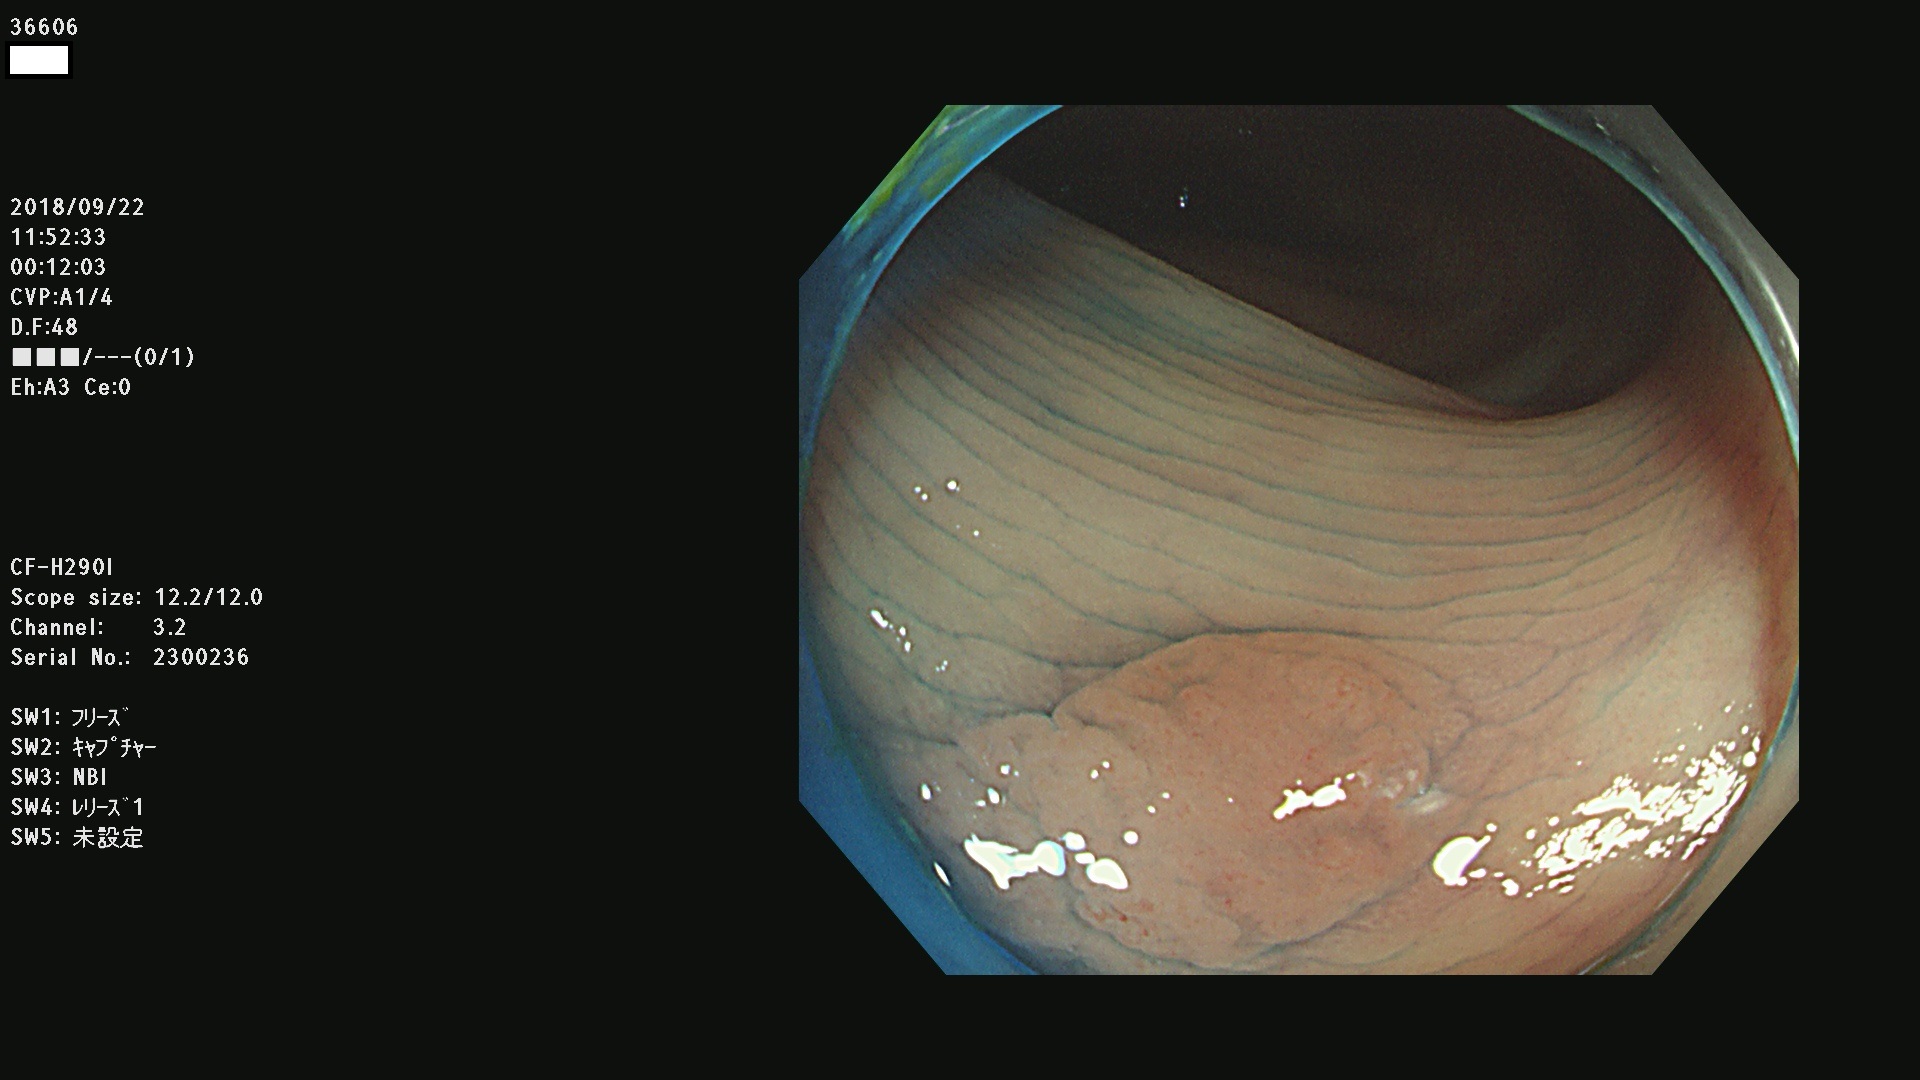

36600 36601 36603 36605 36606 36608 36609 36610 36611 36612 36613 36615 36617 36620 36621 36624 36625 36626 36627 36628 36629 36631(SSAPのみ) 36632 36633 36634 36636(SSAPのみ) 36637(SSAPのみ) 36639 36640 36642 36643 36644 36646 36647 36648 36649(SSAPのみ) 36650(SSAPのみ) 36652 36653 36654 36655(SSAPのみ) 36656 36657 36658 36659 36660 36661(SSAPのみ) 36665 36668 36669 36672 36673 36676 36677 36678 36679 36681 36682 36683 36684 36685 36687(SSAPのみ) 36691 36692 36693 36694 36695 36696 36697 36699(SSAPのみ)

発見困難で危険性の高い平坦型病変(上記100名より抽出)